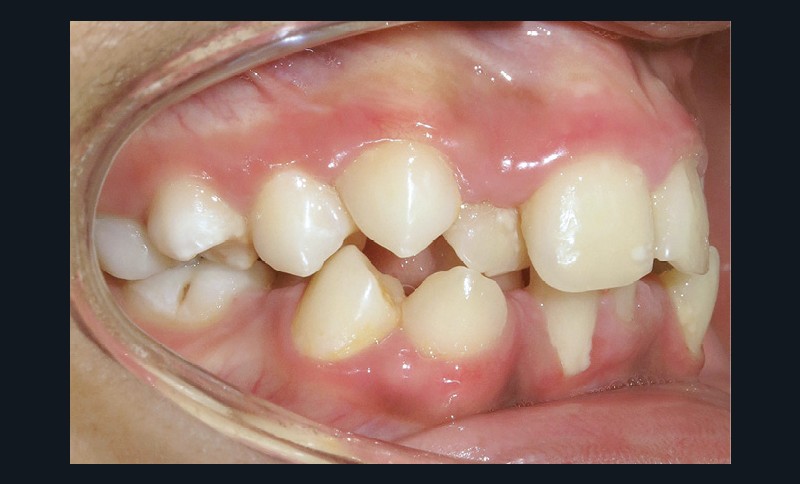

En denture adulte, la DDM est majeure avec un déficit de place estimé de 13 mm à la mandibule. Les lésions carieuses ont aussi touché les premières molaires permanentes maxillaires. La 26 a été avulsée et la 27 a pris sa place. Côté controlatéral, la 16 est fortement délabrée, rendant impossible sa conservation. Les molaires ayant plus mésialé à l’arcade mandibulaire, les rapports occlusaux sont de classe III. Les incisives sont versées vers l’avant, mais nous pouvons considérer qu‘il s’agit d’une biproalvéolie ethnique. Du point de vue squelettique, le patient présente une classe II squelettique par rétromandibulie sur un schéma facial hyperdivergent (fig. 1a-j).